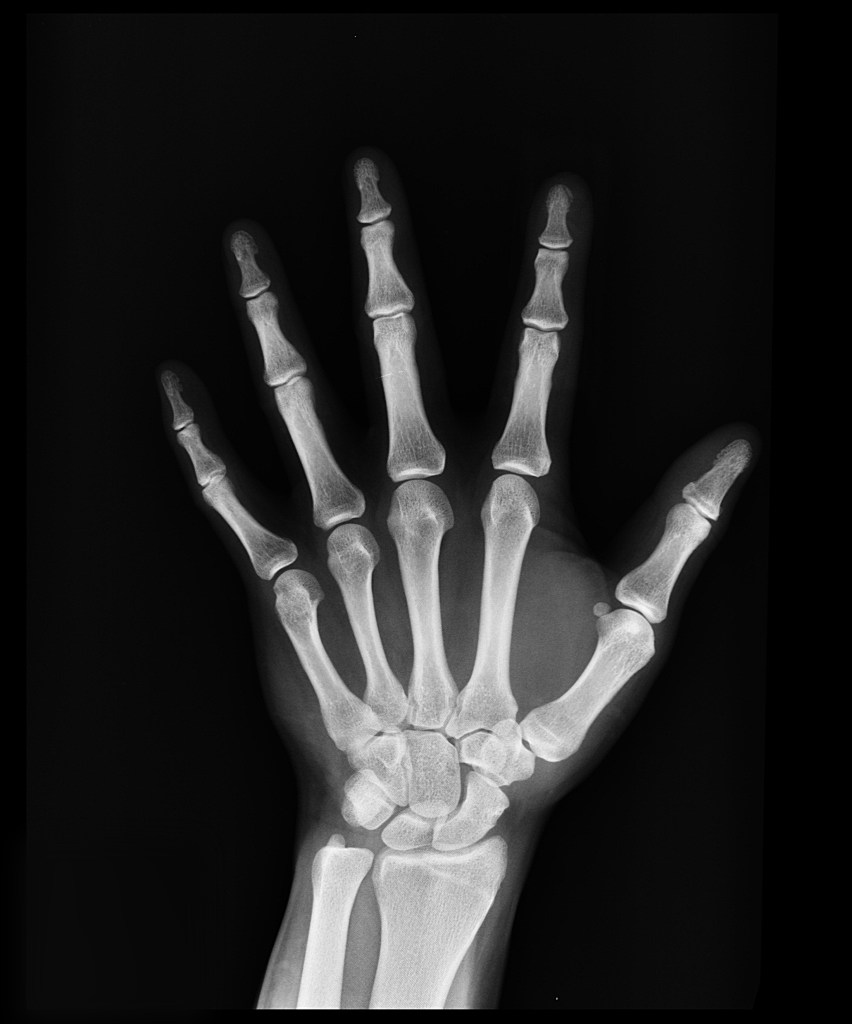

Mi reumatóloga lo vio claro nada más leer los análisis, escuchar mis síntomas y examinar mis manos. A su juicio lo mío era artritis reumatoide. Esos nudillos engrosados que habían hecho que de pronto no pudiera ponerme muchos de mis anillos favoritos porque no me pasaban de la mitad del dedo le dieron toda la información que necesitaba para diagnosticarme. Pero ese examen ocular de mis manos le dio más información y amplió mi diagnóstico a algo que yo no esperaba.

Para poder determinar el grado de avance de la enfermedad y dado que nunca hasta entonces se habían tomado registros para ver la evolución se tomaron fotografías y se hizo una resonancia magnética de mis manos para ver hasta qué punto el tejido de las articulaciones estaba dañado. El resultado de esa resonancia determinaría el tratamiento.